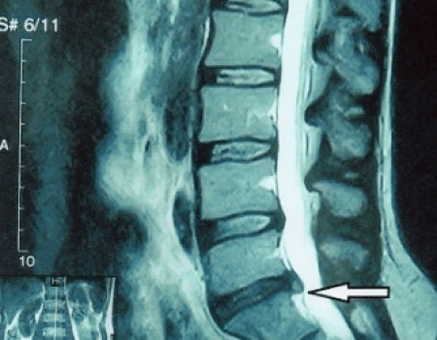

In typical cases, osteoarthritis of the cervical and cervicothoracic spine occurs as described above.Therefore, the main stage of diagnosis remains the identification of the patient's complaints, determining the presence of concomitant muscle spasms by simple palpation of the muscles along the spine.Can the diagnosis of osteoarthritis be confirmed with an X-ray?

An “X-ray” of the cervical spine and even with functional tests of flexion and extension do not show cartilage because their tissue transmits X-rays. Despite this, based on the position of the vertebrae, one can draw general conclusions about the height of the intervertebral discs, the general straightness of the physiological curvature of the neck - scoliosis, as well as the presence of marginal growths on the vertebrae with prolonged irritation of their surfaces by fragile and dehydrated intervertebral discs.Functional tests can confirm the diagnosis of cervical spine instability.

Since the disc itself can only be seen using CT or MRI, magnetic resonance imaging and X-ray computed tomography are indicated to clarify the internal structure of the cartilage and components such as protrusions and herniations.Therefore, with the help of these methods, the diagnosis will be made accurately and the results of the CT scan will be an indication, even a local guide for surgical treatment of hernia in the neurosurgery department.